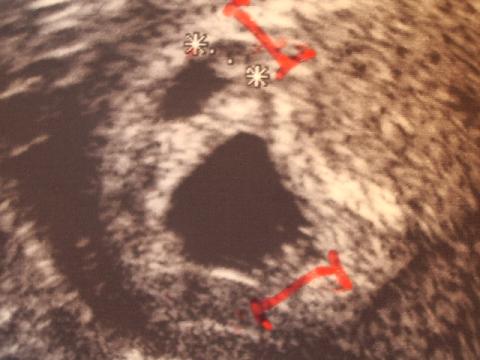

Schaut mal: So sieht d. US von gestern morgen aus!

Das kann dann doch nicht in 2 Stunden weggewesen sein!!!!

(das obere in d. kleinere FH ist d. Embryo, der 2 Stunden später verschwunden sein soll!) Beide Embryonen sind mit rot markiert worden. (liegen VOR d. Striche)!